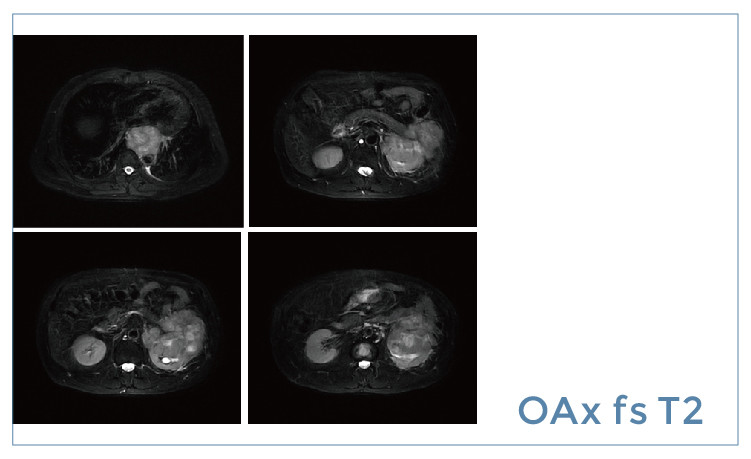

【朗润影像档案】磁共振影像病例分享(编号20190426)